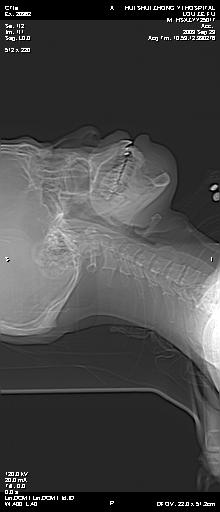

标题: CT22429:患者男性,35岁,因下颌部软组织肿胀并疼痛2月余, [打印本页]

标题: CT22429:患者男性,35岁,因下颌部软组织肿胀并疼痛2月余,

下颌骨囊性性膨胀性骨质破坏,考虑造釉细胞瘤